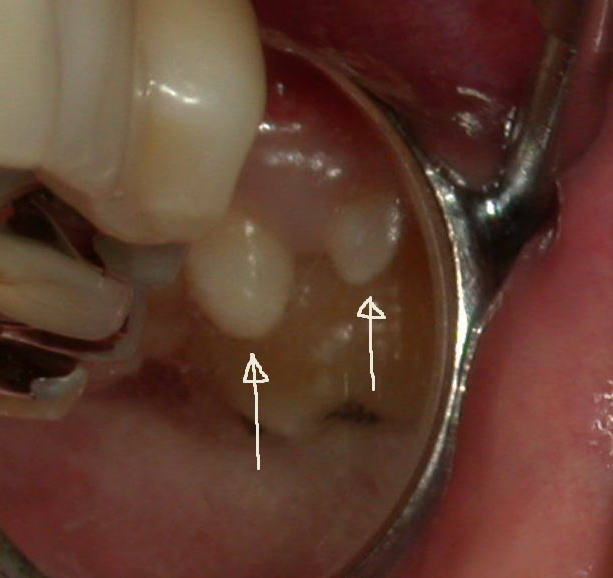

今度は左側の上の第二大臼歯の外側に歯が出てきました。それも二本です。

写真の様に小さい歯が2本生えています。まるでムーミンに出てくるニョロニョロ!?のような感じて仲良く並んで生えています。

左写真の丸いミラー部の拡大